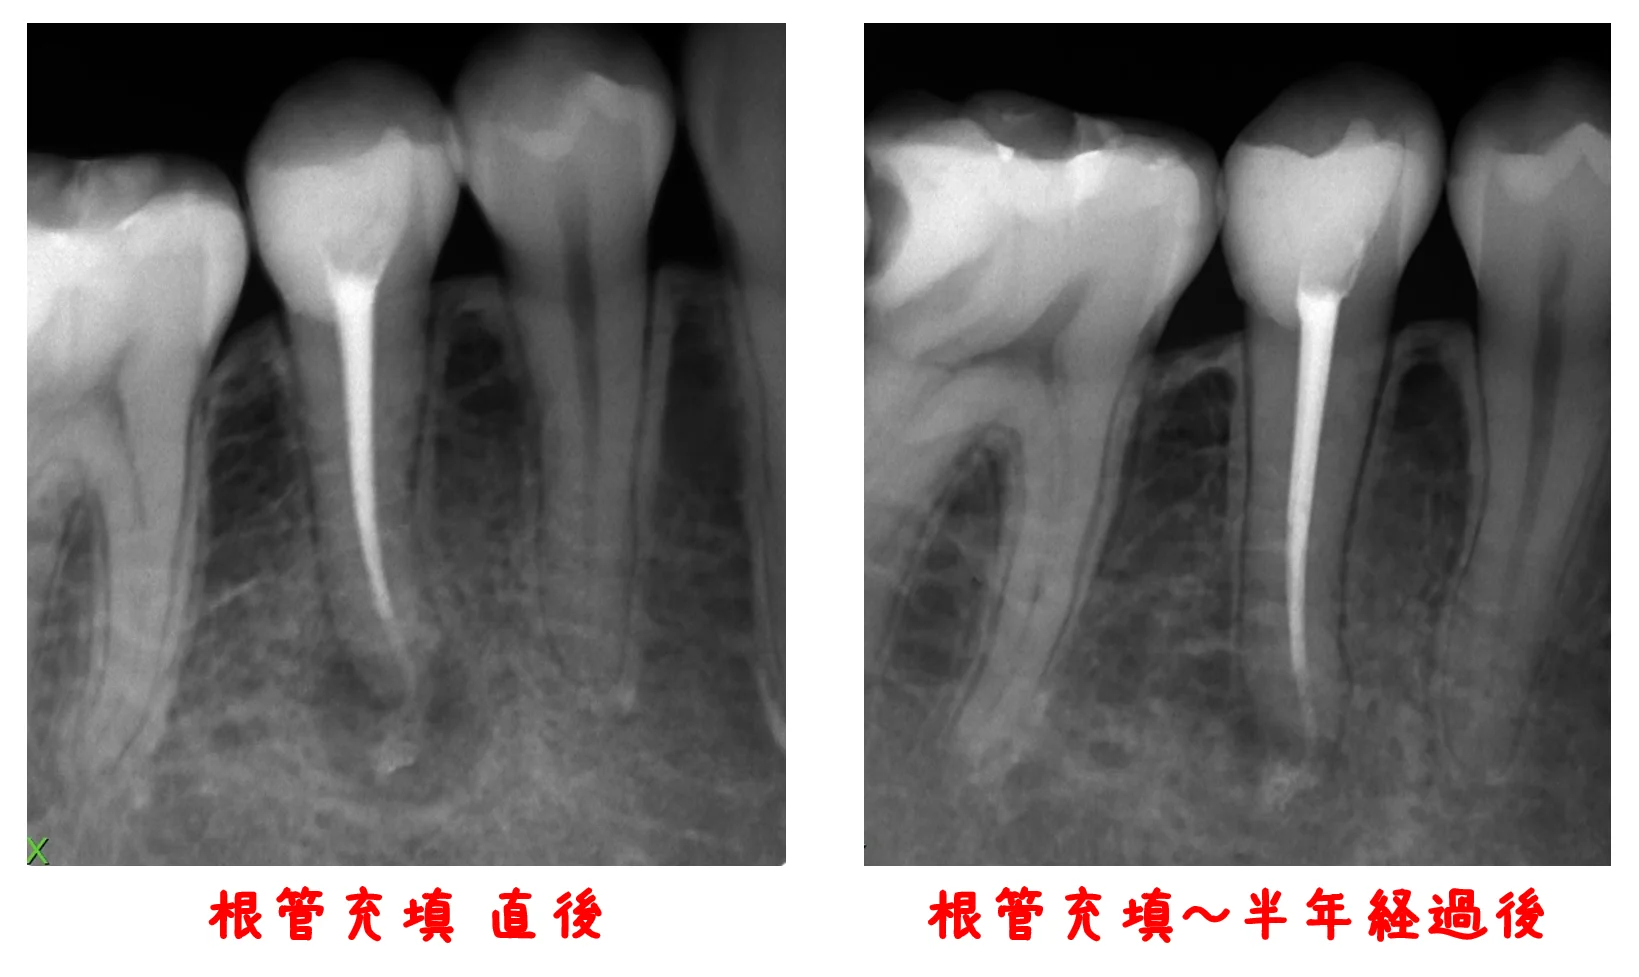

さて、今回は前回の「神経の治療③(リンクが開きます)」でお見せした患者さんの根管充填を行ってから半年が経過したレントゲンを撮らせて頂いたので、そちらを載せたいと思います。

根の先の黒い部分が、膿によって骨が溶かされている所です。

右の半年経過後のレントゲンでは、黒い部分が随分と小さくなっているのが分かるかと思います。

非常に順調に治ってきてくれているようで良かったですヽ(゚∀゚)ノ パッ☆

またしばらくしてからレントゲンを撮らせてもらい、その経過を確認したいと思います。